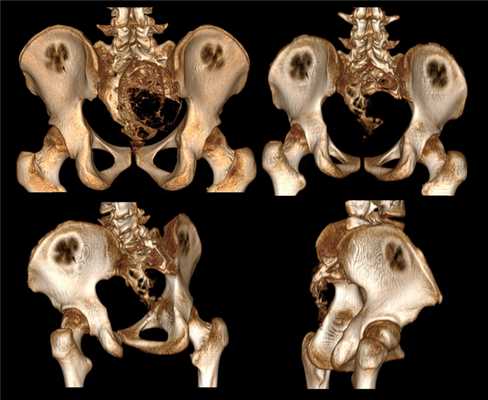

Наиболее часто аневризмальные костные кисты располагаются в губчатых костях (позвонки, кости таза, коленный сустав). Первые симптомы - скованность, дискомфорт, незначительная боль в поражённом сегменте при движении. После прекращения нагрузки симптомы исчезают. Со временем боль нарастает и становится постоянной. Дальнейшие проявления зависят от локализации аневризмальной кисты кости.

В позвоночнике в основном встречаются аневризмальные кисты. Они представляют собой многокамерные полости, заполненные кровянистым содержимым. Этот вид новообразований склонен к быстрому росту, что провоцирует появление характерных симптомов и заставляет больных обращаться к ортопеду-травматологу, вертебрологу или неврологу. Но также из-за активного увеличения размеров аневризмальные кисты создают опасность развития осложнений, ведь это приводит к истончению стенок костей, снижению их прочности, вздутию и нарушению пропорций. В результате резко возрастает риск переломов позвоночника и развития стеноза спинного мозга, что чревато тяжелыми неврологическими расстройствами.

В зависимости от расположения различают кисту тела позвонка или его дуги, хотя в большинстве случаев поражается именно дуга, но со временем в результате роста она может распространяться в ножки и тело позвонка. Деформируя их, образование может выпячиваться в позвоночный канал и провоцировать компрессию спинного мозга или отходящих от него нервных корешков. При этом оно может формироваться в любом отделе позвоночника: шейном, грудном, поясничном и крестцовом. От этого напрямую зависит клиническая картина заболевания.

Аневризмальная костная киста

Опухолевидное жидкостное доброкачественное образование, встречаемое в различных тканях нашего организма, называется кистой. Довольно редким видом кистообразований является аневризмальная костная киста, представляющая собой большие тонкостенные полостные разрастания, заполненные кровью и сообщающиеся между собой. Локализация данного вида образований наблюдается в позвоночном столбе и тазобедренном суставе нашего организма. Патология, развивающаяся в позвоночном столбе, зачастую наблюдается в грудном и шейном его отделах, поражая порой до шести позвонков. Чаще всего диагностируется у детей и подростков.

Патология возникает в следствии кровоизлияния, способствующее быстрому росту образования и разрушению сустава. В определённое время наблюдается процесс характерной стабилизации. Развитие патологии сопровождается ярко выраженной симптоматикой, которая заметно нарастает с течением заболевания.

Встречается реже солитарной. Обычно возникает у девочек 10-15 лет. Может поражать кости таза и позвонки, реже страдают метафизы длинных трубчатых костей. В отличие от солитарной костной кисты, как правило, возникает после травмы. Формирование полости сопровождается интенсивными болями и прогрессирующим отеком пораженной области. При осмотре выявляется местная гипертермия и расширение подкожных вен. При локализации в костях нижних конечностей отмечается нарушение опоры. Заболевание нередко сопровождается развитием контрактуры близлежащего сустава. При костных кистах в позвонках появляются неврологические нарушения, обусловленные сдавление спинномозговых корешков.

Различают две формы аневризмальных костных кист: центральную и эксцентрическую. В течении болезни выделяют такие же фазы, как и при солитарных кистах. Клинические проявления достигают максимума в фазе остеолиза, постепенно уменьшаются в фазе отграничения и исчезают в фазе восстановления. На рентгенограммах в фазе остеолиза выявляется бесструктурный очаг с внекостным и внутрикостным компонентом, при эксцентричных кистах внекостная часть по размеру превышает внутрикостную. Надкостница всегда сохранена. В фазе отграничения между внутрикостной зоной и здоровой костью образуется участок склероза, а внекостная зона уплотняется и уменьшается в размере. В фазе восстановления на рентгенограммах обнаруживается участок гиперостоза или остаточная полость.